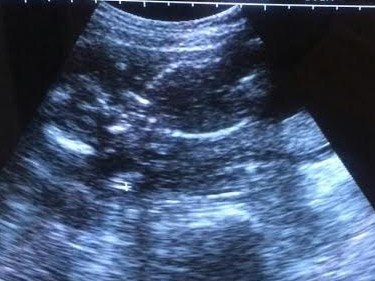

21 weeks, boy or girl???

Attachment 30920

Boy or girl??

No good potty shot there